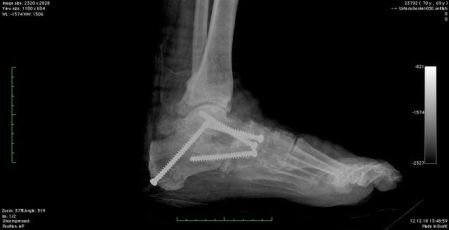

Kalkaneusosteotomie (Fersenbeinverschiebung)

- Durchtrennung und mediale Verschiebung des Fersenbeins

- Korrektur der Valgusstellung der Ferse

- Fixierung meist mit Titanschrauben

Evans-Osteotomie

- Verlängerung des äußeren Fersenbeins

- Beseitigung der Vorfußabduktion

- Einsatz bei jungen, flexiblen Deformitäten oder als Ergänzung

Zentrale Fersenbeinosteotomie

- Korrektur der Valgusstellung des Fersenbeines sowie die Verlängerung des Fersenbeines (Korrektur der Vorfußabduktion) mit nur einer knöchernen Umstellung

Cotton-Osteotomie

- Knochenkeil zur Anhebung des medialen Fußstrahls (meist am Os cuneiforme)

- Verbessert das Gewölbe, besonders in Kombination mit Sehnentransfer

Die Naviculocuneiforme Korrekturarthrodese

- Bei Plattfüßen bedingt durch Instabilität im „Tarsus“

- Arthrodese (Versteifung) von ohnehin nicht „essentiellen“ Gelenken in korrigierter Stellung

- Meist für junge sehr flexible Plattfüße ausreichend

- Kombination mit Korrekturarthrodese zwischen Mittelfuß und Fußwurzel möglich (Miller-OP)

Triple-Arthrodese

- Versteifung dreier Rückfußgelenke (Talonavikular-, Kalkaneokuboid- und Subtalargelenk)

- Einsatz bei fortgeschrittener Arthrose, rigider Fehlstellung oder fortgeschrittenem Alter

- Ziel: Schmerzfreiheit und belastbare Rückfußstatik